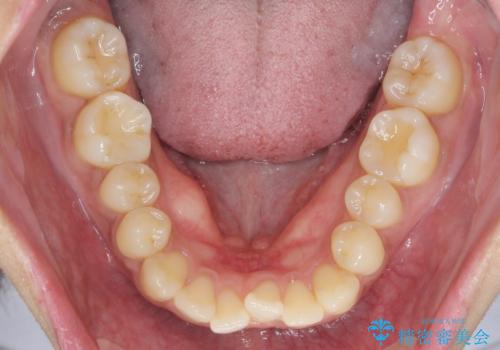

前歯のがたつきをすっきり マウスピース矯正

- 長年気になっていた前歯のがたつきをマウスピース矯正で治したい!と希望され来院されました。

奥歯の噛み合わせには問題がなく、前歯のがたつきの改善のみで十分に審美的な結果が得られるため、ワイヤーではなくマウスピース矯正での治療を計画します。

しっかりと前歯のがたつきは改善し見た目が大きく良くすることができました。